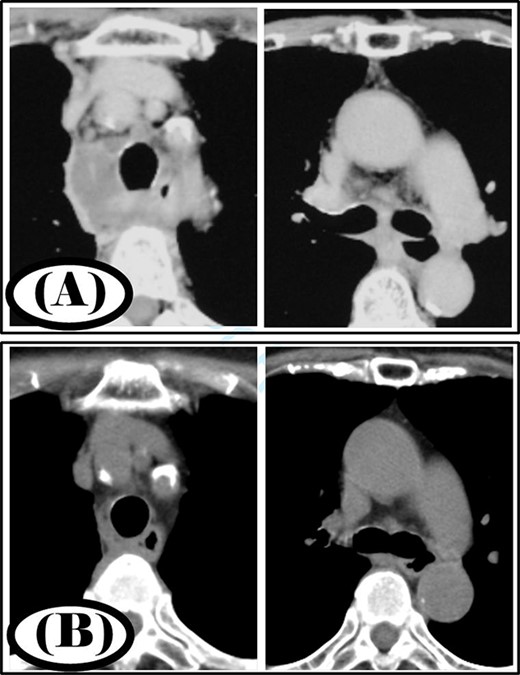

A 35-year-old man was diagnosed with a cervical abscess and initially underwent cervical drainage. The next day, he developed upper gastrointestinal perforation that was covered with an omental patch in a laparoscopic procedure. The cervical abscess did not improve and chest CT revealed that the infection had developed into the mediastinum (Fig. 2A). The patient was diagnosed with type II DNM and underwent mediastinal drainage using a cervical approach 3 days later. Initial antibiotic therapy consisted of meropenem at 9 g/day for 6 days as broad-spectrum antibiotic therapy. After Streptococcus anginosus group was detected in the mediastinal abscess cavity, the antibiotic was changed to ampicillin/sulbactam 12 g/day and was administered via intravenous infusion for 15 days. Continuous irrigation with saline (2 L/day) was initiated immediately post-surgery; however, 500 ml per day of saline was used for irrigation on the first 4 days. The duration of irrigation, drainage and hospital stay were 4, 16 and 39 days, respectively. Five weeks post-surgery, cervicothoracic CT showed no abscess cavity and an improvement in infection (Fig. 2B).

Case 2: pre- and post-treatment cervicothoracic CT; (A) pre-operative cervicothoracic CT and (B) cervicothoracic CT 5 weeks after treatment.